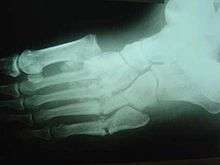

Destroyed Tarsometatarsal joints in the medial left foot, with fracture and dislocation of fragments; these are classic findings. Also note loss of the foot arch and acquired flat foot (pes planus) deformity.